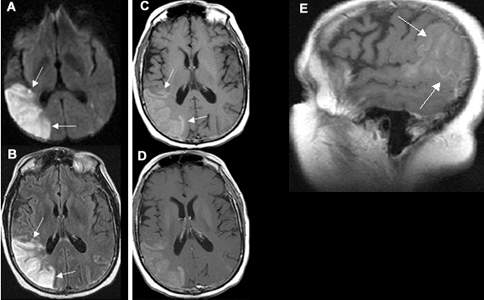

Acute One Day Old Infarction Involving the Right Middle Cerebral Artery (MCA) Territory

A. Diffusion weighted image shows area of infarct as bright signal.

B. T1 image shows no evidence of blood in the area of infarct (blood would appear as white).

C. Post contrast coronal image shows vascular enhancement in the area of infarct.

D. MR angiography shows right middle cerebral artery branches to be narrower in calibre, as compared to left.